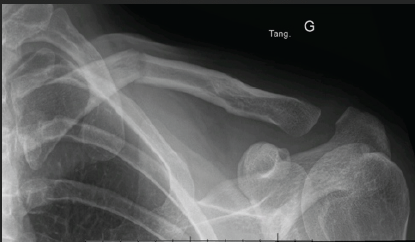

Medial Clavicle Fracture with Posterior Dislocation of the Ipsilateral Acromioclavicular Joint Following Skiing Trauma

Braghis Vlad , Palladino Stefano , Debordes Pierre Antoine , Lacheux Nathan , Jany Richard

………………………………p.32-35